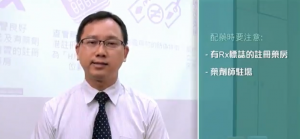

藥到病除:標靶藥治ALK肺癌療效佳 肺癌是本港第二常見癌症,一六年的癌症新症中,有百分之十五點七是肺癌個案。肺癌大致分兩大類,包括非小細胞肺癌(ALK)和小細胞肺癌,前者約佔肺癌的八成。在ALK患者中,表皮生長因子基因突變的發生率在亞裔患者佔三成至四成,出現突變的基因會令腫瘤生長速度不受控地增加。… 詳情 如何辨認正貨藥物及儲存藥物 本港發現市面有藥物懷疑受霉菌污染需全面回收,海關亦掃蕩大批「水貨」藥物,接二連三的事件,引爆藥物安全疑慮。被檢獲的水貨藥物中,更發現一些針對高危患者的藥物,如薄血藥,一旦患者服食問題藥物,隨時引致中風「出事」。有見及此,影片教育患者及市民分辨正貨藥物,及妥善儲存藥物的方法,確保藥物安全。 詳情

如何辨認正貨藥物及儲存藥物 本港發現市面有藥物懷疑受霉菌污染需全面回收,海關亦掃蕩大批「水貨」藥物,接二連三的事件,引爆藥物安全疑慮。被檢獲的水貨藥物中,更發現一些針對高危患者的藥物,如薄血藥,一旦患者服食問題藥物,隨時引致中風「出事」。有見及此,影片教育患者及市民分辨正貨藥物,及妥善儲存藥物的方法,確保藥物安全。 詳情 藥物發霉食壞人藥劑師:家居藥物儲存方法謬誤多 近日消化藥物「易消達」(Enzyplex)被驗出含有真菌紅麴霉菌,衞生署調查事件後,同意由持牌藥物批發商耀南洋行,從市面回收所有批次的易消達藥片。 詳情